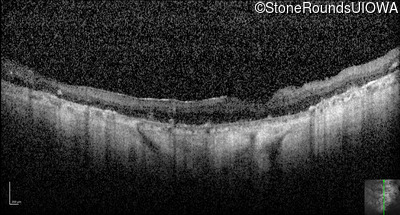

Optical Coherence Tomography - Right - Hand Motion

Exemplar / OCT Stack